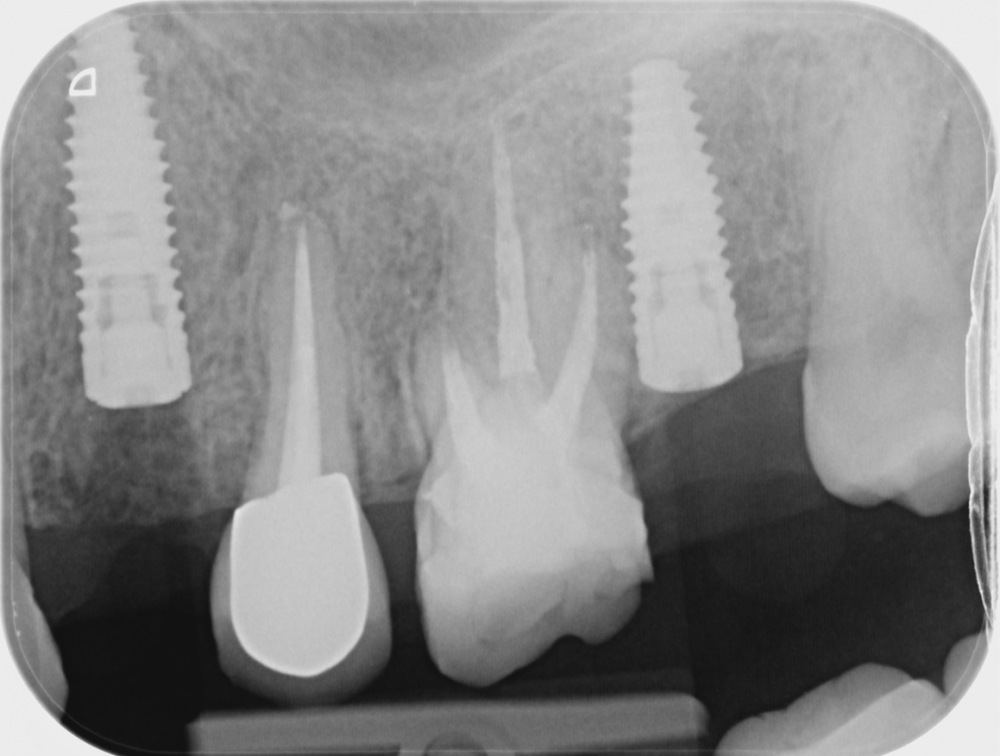

lola-1234 Опубликовано 22 июля, 2021 Поделиться Опубликовано 22 июля, 2021 Здравствуйте, дорогие доктора! Очень нуждаюсь в вашем мнении. Поставили мне сегодня два импланта. Когда увидела снимок установленных имплантов, засомневалась правильно ли врач их установил. Четверка была удалена 2 месяца назад, корни зуба были такой же длинны, что и у пятерки. 1. Как мне кажется, врач установил имплат очень глубоко,под самую гайморовую пазуху. Врач сказал, так как у меня было воспаление после удаление зуба, , поэтому он врутил поглубже, там кость "получше" . Не разумней было бы, просто подождать с имплантацией пару месяцев, и затем вкрутить имплант не столь инвазивно? имплант был 12мм, радиус 4 2. хорошо ли стоит имплант вместо 7ки? Всем спасибо :) Ссылка на комментарий